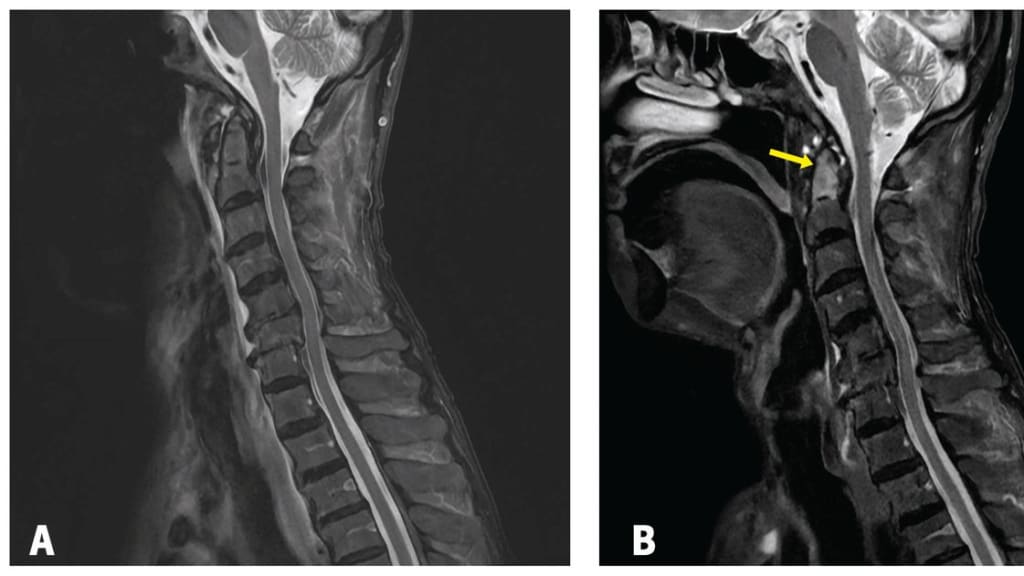

Ein 86-jähriger Mann aus dem japanischen Fukui kommt in die Notaufnahme, da er unter Fieber, Kopfschmerzen, Nackensteifigkeit und eingeschränkter Halsrotation leidet. Die Symptome haben 2 Wochen nach einer Zahnentfernung begonnen. Um einer Infektion vorzubeugen hat der Patient über 10 Tage 300 mg Cefcapen-Pixovil eingenommen.1

Abb. 1 A) MRT-Scan bei Aufnahme B) MRT-Scan 1 Monat später

© Hayashi K et al. CMAJ 2025; 197(27): E811-E812.